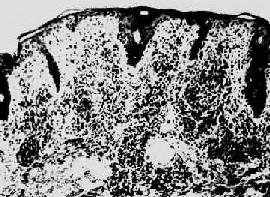

梅毒疹

图18-26 梅毒疹

真皮呈致密的淋巴细胞及浆细胞浸润(采自Muir)

第二期梅毒第一期梅毒如不治疗,即使下疳愈合,潜伏于体内的螺旋体仍能继续繁殖,在感染后第8~10周左右大量进入血循环,引起全身广泛性皮肤粘膜病变,即梅毒疹(syphilid)。通常表现为口腔粘膜红斑丘疹、躯干、四肢、掌心和足心的斑疹、丘疹和口唇、外阴、肛周的扁平湿疣(condyloma lata)。后者表现为暗红色突起的平坦斑块。所有梅毒疹的组织学变化皆为淋巴细胞和浆细胞浸润构成的非特异性炎及闭塞性血管内膜炎和血管周围炎(图18-26),扁平湿疣则尚有表皮增生和角化不全。凡梅毒疹病灶内皆有苍白螺旋体。第二期梅毒有全身性淋巴结肿大,镜下为非特异性炎。少数患者可发生亚急性脑膜炎虹膜炎肝炎,以及免疫复合物反应所引起的膜性肾小球肾炎。梅毒疹也可不治“自愈”,但患者实际陷入隐性梅毒阶段,若不治疗,多年后30%的患者将发生第三期或晚期梅毒。第二期梅毒若予治疗,将阻止其向第三期梅毒发展。